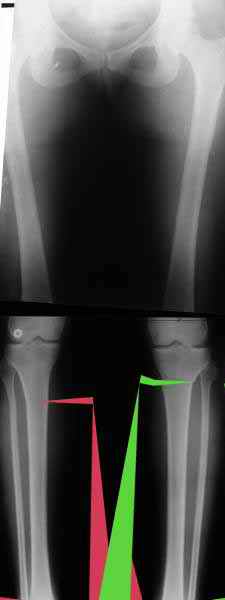

Вот, с учетом и без учета, и на разных уровнях...

Из приведнной схемы не совсеим понял что означают разноцветные линии.

И зачем латерализация периферического фрагмента. Я всегда делаю медиализацию. См схему. И для данного случая медиализация подходит как нельзя лучше.

a> Из приведнной схемы не совсеим понял что означают разноцветные линии.

Черные - это нынешняя механическая ось. Красные - это планируемая правильная ось.

a> И зачем латерализация периферического фрагмента.

;-) Читайте Палея. Стр. 114-115.

a> Я всегда делаю медиализацию. См схему. И для данного случая

Медиализация - это чисто эстетический прием, как я понимаю. Поскольку если делать остеотомию ниже вершины деформации, для восстановления оси надо делать смещение по ширине, в данном случае как раз латерализацию.

А вот на схемке без осей - там на разных уровнях (который правильнее?) устранение варуса чисто открытым клином без медиализации-латерализации. Если как-то так сделать - этого недостаточно будет?